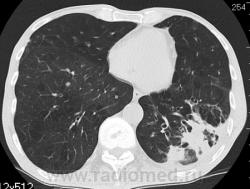

На фоне консолидации полость без содержимого. Может быть всё что угодно, что сопровождается деструкцией. Нужны ещё томограммы в лёгочном окне.

Изображения выставлены все. Ваше мнение уважаемые коллеги?

Туберкулёз.

Туберкулёз?

Это КТ 2-летней давности и попало оно мне в руки, после недавнего прохождения контроля пациентом, когда мы стали перед вопросом о специфическом / не специфическом процессе.

Тогда, пациента 2 месяца лечили от пневмонии, лечили интенсивности, стационарно, в серьёзном учреждении.

Нет опыта работы на цифровых аппаратах: дефекты правого нижнего лёгочного поля объясняются артефактами?

Предположу аспергиллез